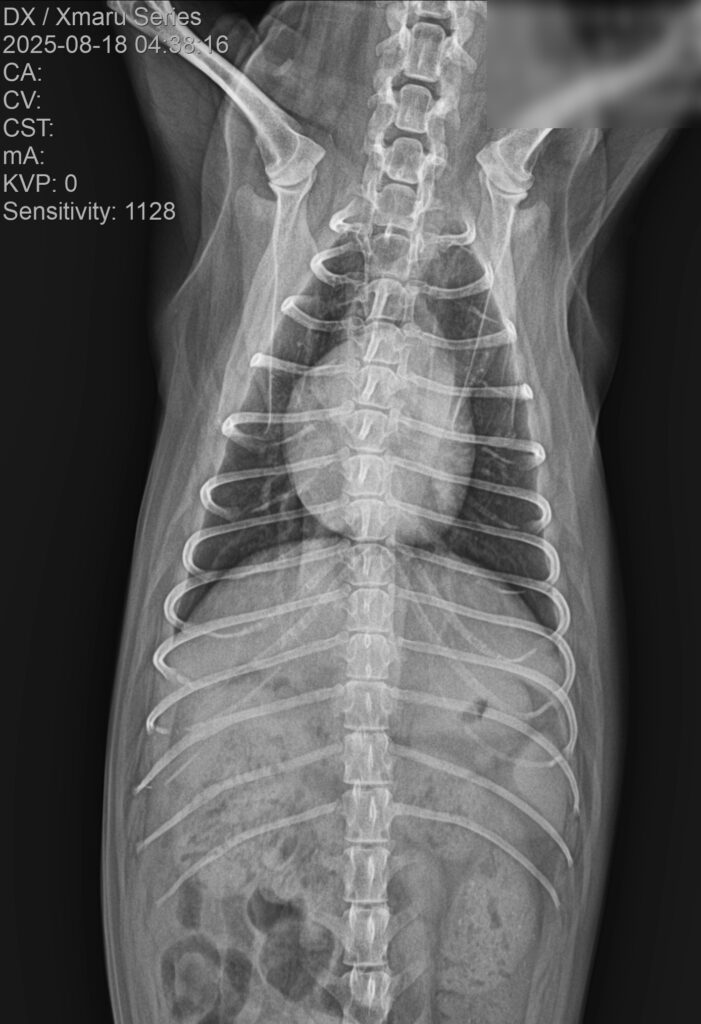

3. 흉부 방사선(X-ray) 검사

흉부 방사선 검사에서는 폐야 전반에 걸친 광범위한 침윤 소견이 관찰되었습니다.

내원 당시 흉부 방사선 사진/ 출처: 강서YD동물의료센터